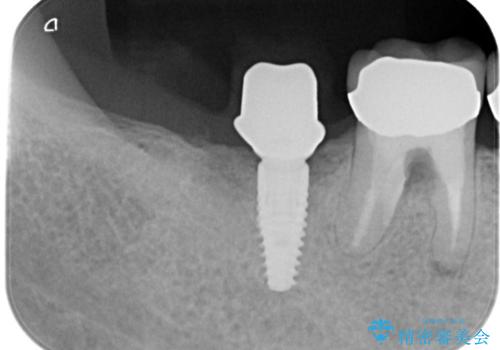

- 「他院で治療した被せ物が外れた」を主訴に来院された患者様です。診査診断を行い歯の保存が困難だったため抜歯後、インプラントで治療しました。

インプラントを入れるためには十分な骨の高さと幅が必要です。術前に検査を行い必要であれば別途、骨や角化歯肉を増やす治療も行う事があります。

インプラントの土台と被せ物は適合が良い物を制作するため、シリコン印象材を使用し型を取っています。